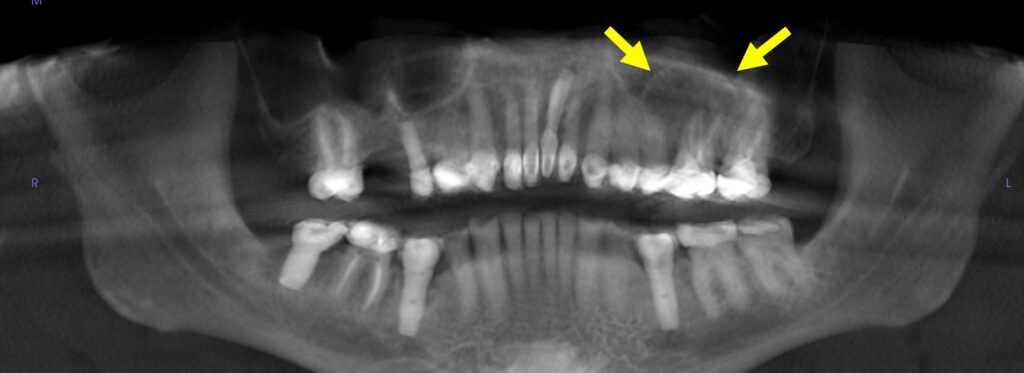

A 9-year-old boy with mild macrocephaly, frontal bossing, and hypertelorism.

41-year-old man seen for recall exam

An asymptomatic 41-year-old man visited the dental office for a regular recall exam.